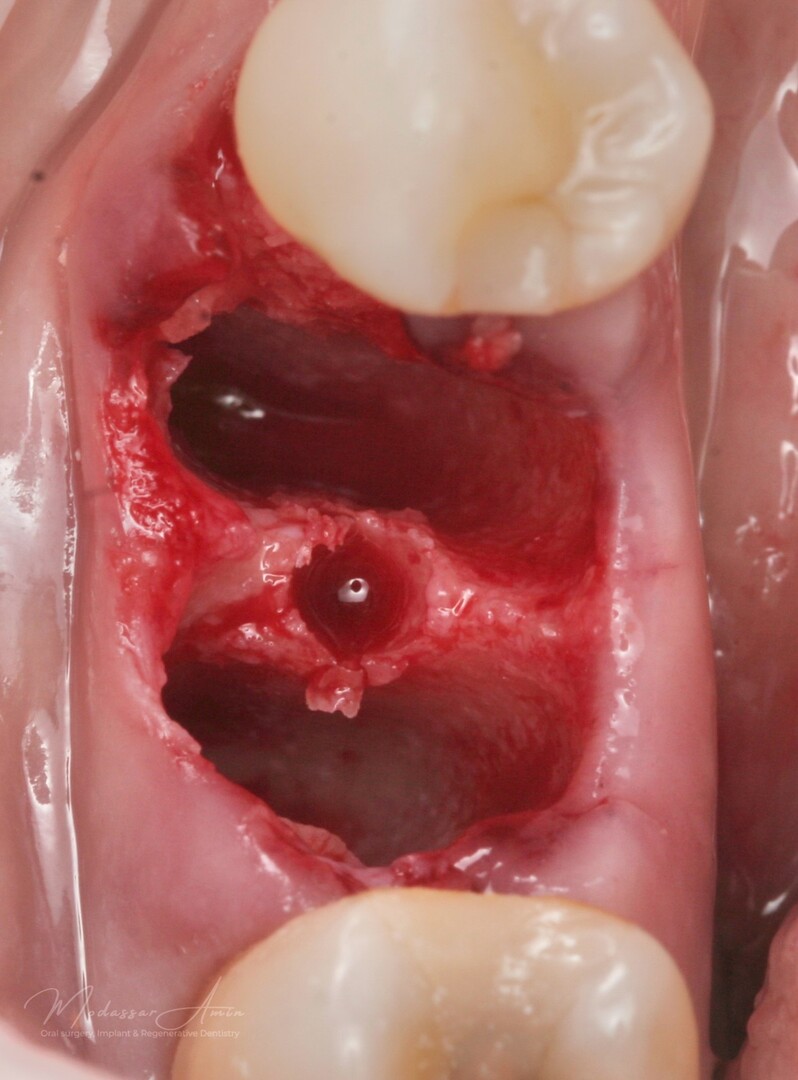

PATIENTFALL

"Pasienten presenterte med tann 46 som ikke kunne bevares grunnet en dyptgående infraksjon inn i furkasjonen. Forholdene lå til rette for en immediate implantatbehandling. Ved hjelp av Versah osseodensifikasjonsbor ble det interradikulære beinet ekspandert på en skånsom og forutsigbar måte, noe som ga høy primærstabilitet (>40 Ncm) til tross for en lokal bendefekt apikalt mesialt etter kronisk apikal periodontitt. Den gode stabiliteten muliggjorde bruk av SSA (Sealing Socket Abutment) for forsegling. På grunn av tynn bløtvevsfenotype bukkalt ble behandlingen supplert med bindevevstransplantat (CTG)"

Påbörjad expansion

Expanderat septum